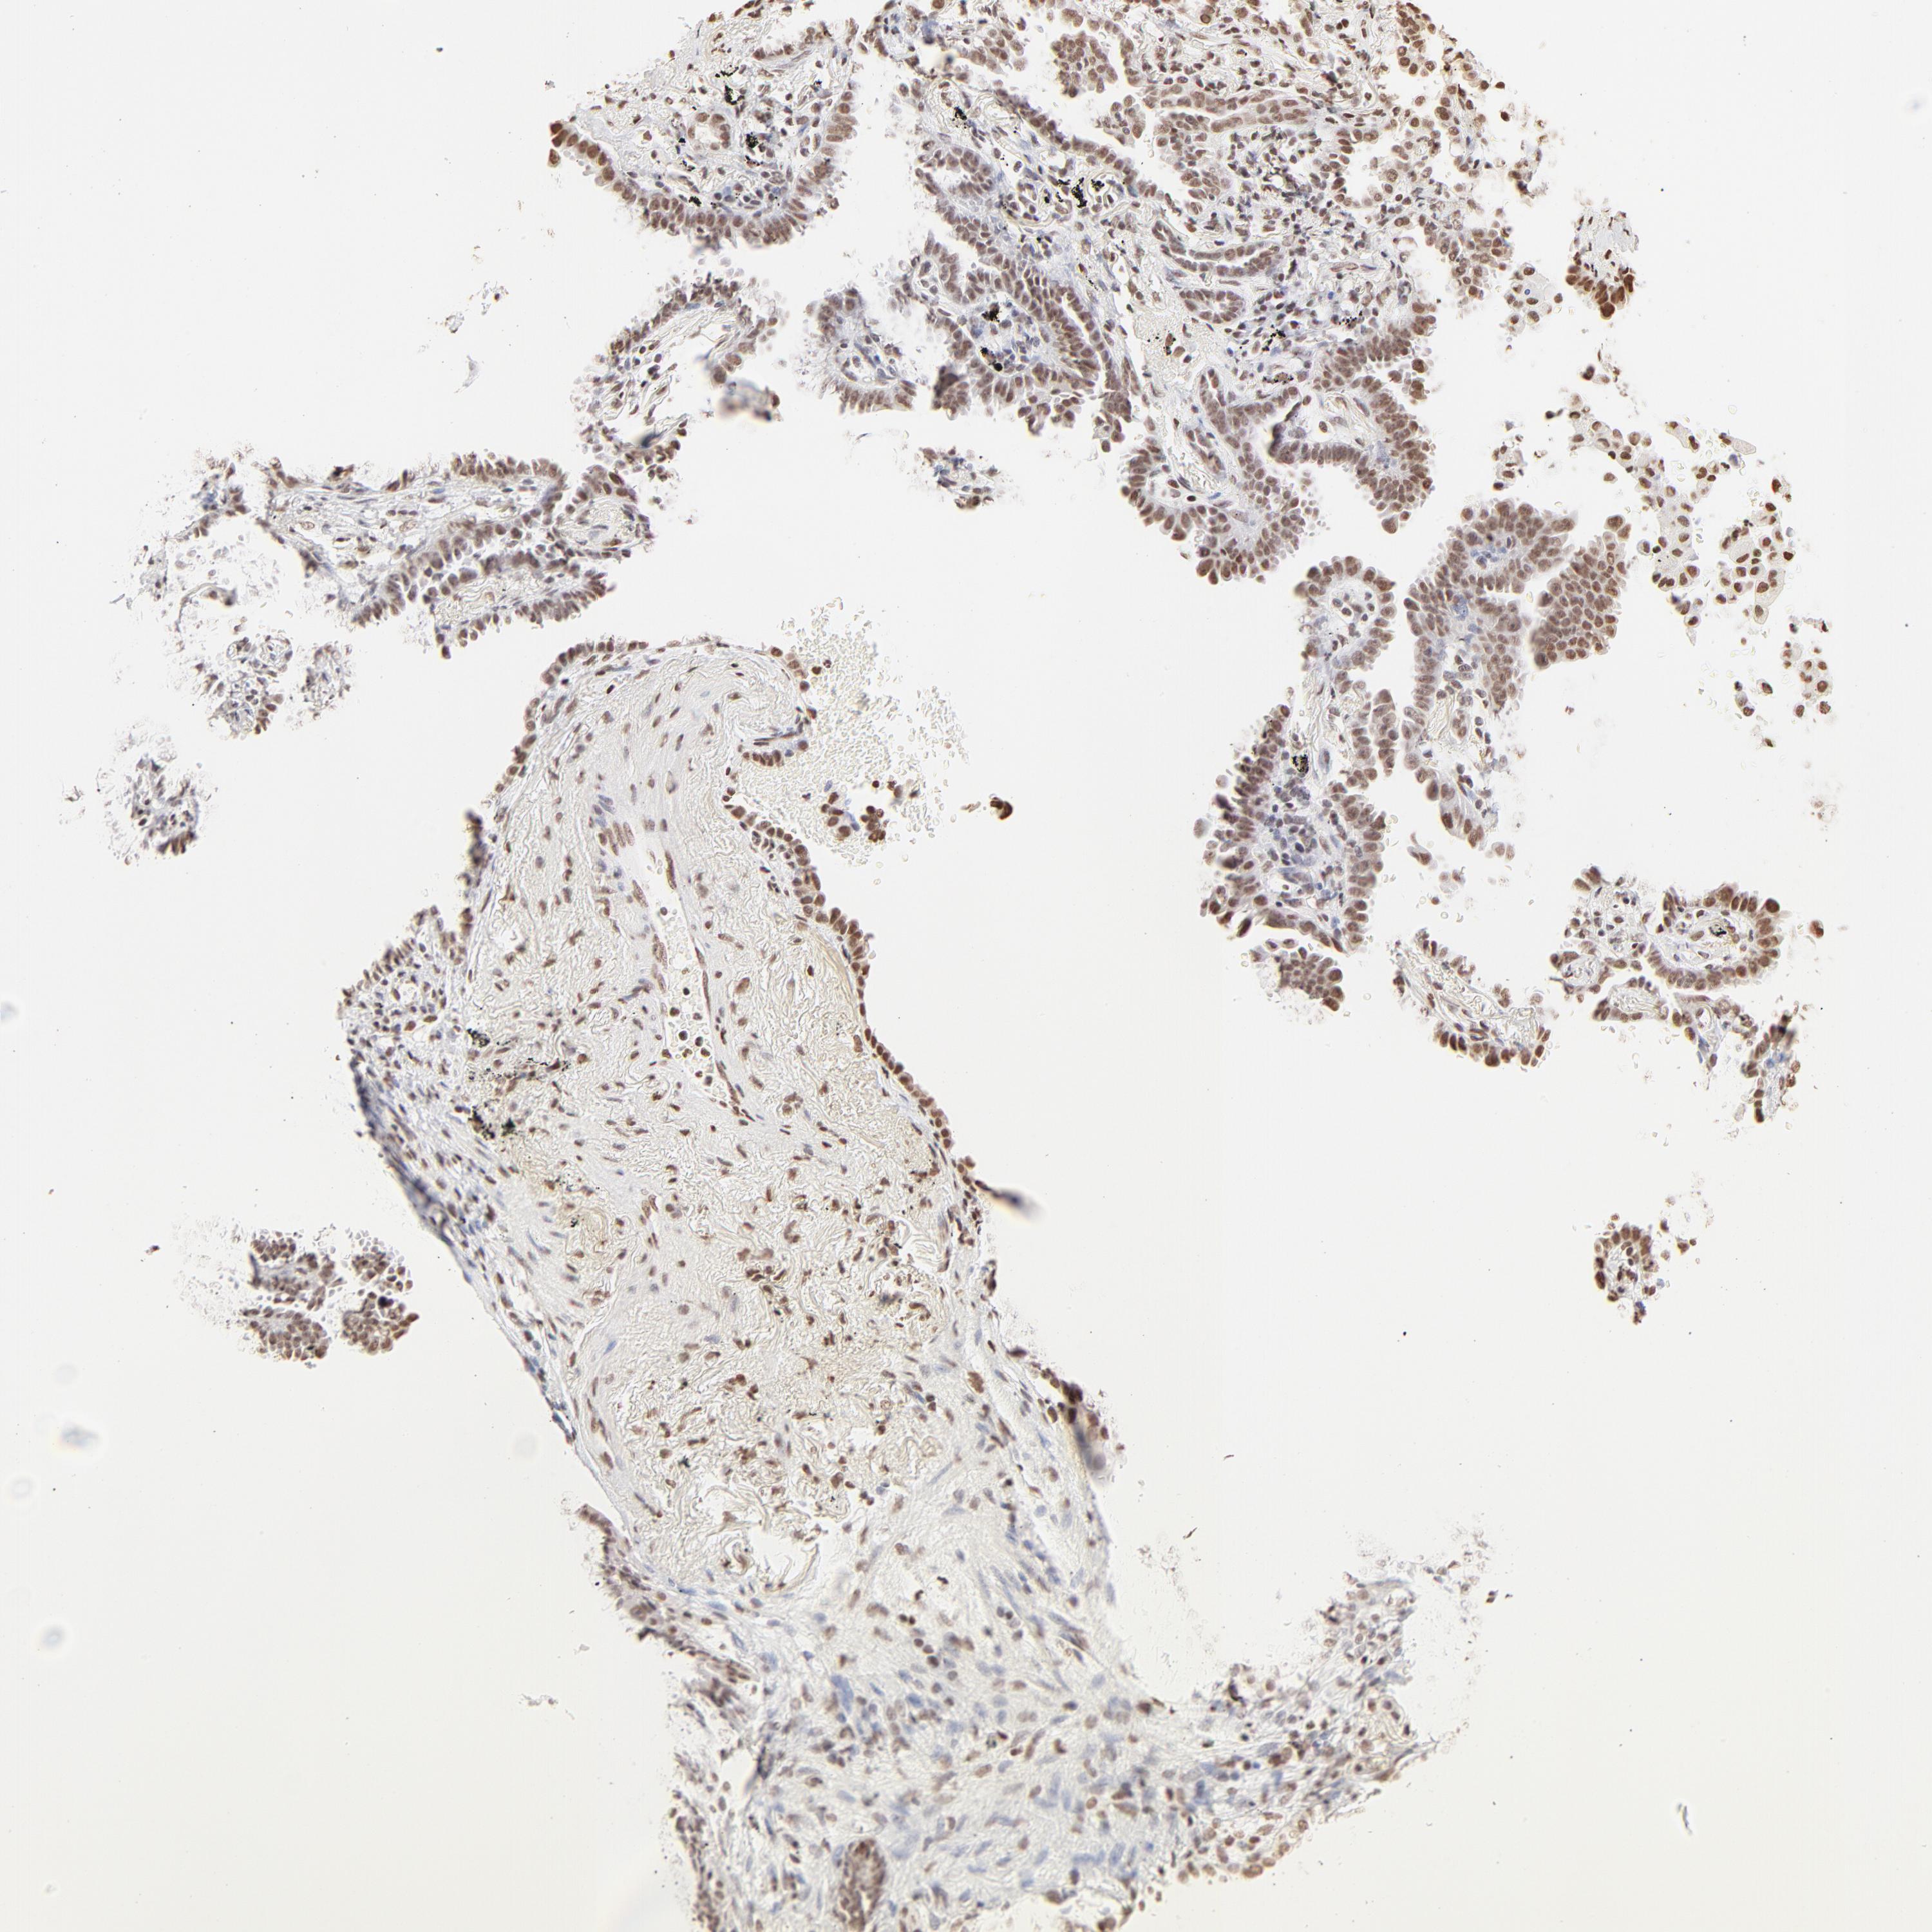

CANCER LUNG CANCER Show tissue menu

LUAD TCGA LUAD VALIDATION LUSC TCGA LUSC VALIDATION PROTEIN LUAD CPTAC PROTEIN LUSC CPTAC PROTEIN EXPRESSION